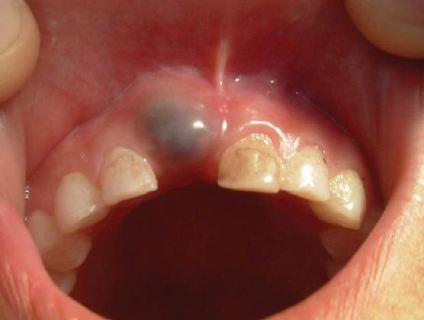

eruption cyst

Children, overlying the crown of erupting deciduous or permanent tooth, subsides whentooth erupts